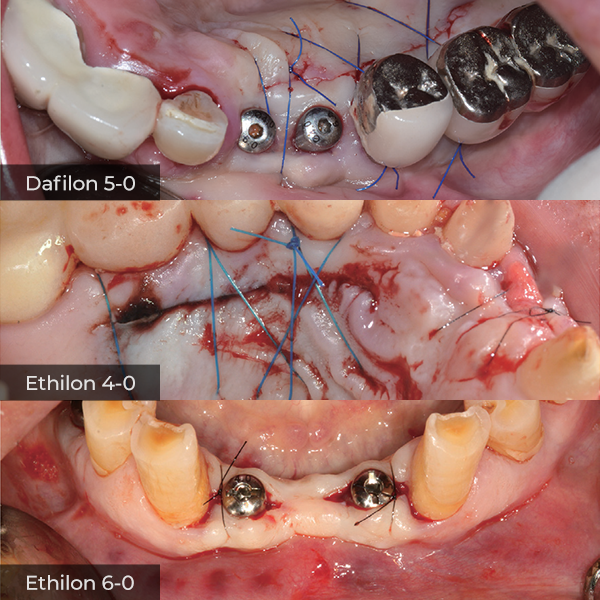

Director’s Clinical Cases

Director’s Clinical Cases